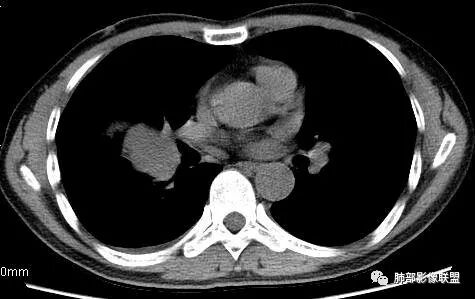

但是现在的片显示,其主体在下叶,中叶支气管壁由下朝上有推移

南边:就不符合这个原理

初学者:如果中叶病灶,叶间裂应该下推,也不会上推

而且支气管內密度较高是粘液栓,远端支气管也是通畅,所以支气管内是因为受压所以痰液引流不畅。

南边:从叶裂的变形,下朝上,越来越朝前扭曲,提示叶裂局部有朝前上推移的趋势

南边:下叶的支气管受压后移、变形

南边:病灶边界清,提示侵袭性弱,膨胀生长为主;这时候我们提示病灶不应该是支气管关系密切,提示间叶来源或胸膜来源

深分叶,警惕恶性